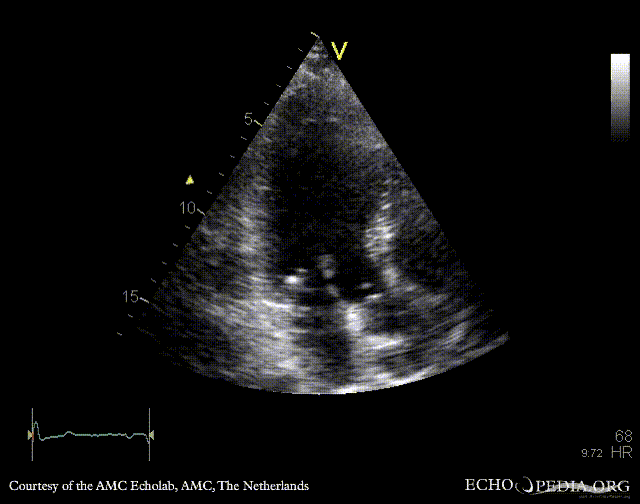

Endocarditis of aortic valve

PLAX: vegetation on aortic valve PSAX: vegetation on aortic valve

E00418.gif E00419.gif